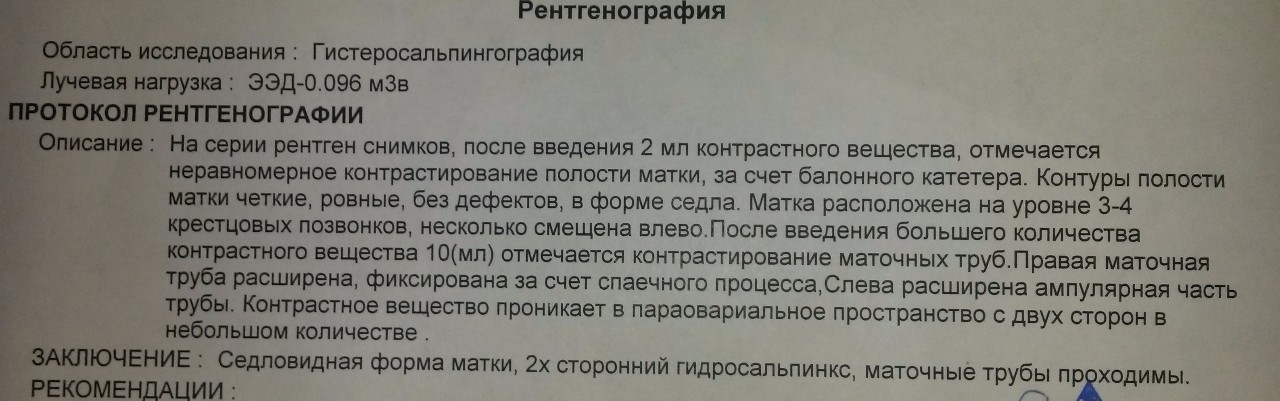

Гистеросальпингография: описание и фотографии